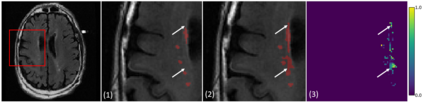

We propose an unsupervised domain adaptation (UDA) approach for white matter hyperintensity (WMH) segmentation, which uses Self-Training with Uncertainty DEpendent Label refinement (STRUDEL). Self-training has recently been introduced as a highly effective method for UDA, which is based on self-generated pseudo labels. However, pseudo labels can be very noisy and therefore deteriorate model performance. We propose to predict the uncertainty of pseudo labels and integrate it in the training process with an uncertainty-guided loss function to highlight labels with high certainty. STRUDEL is further improved by incorporating the segmentation output of an existing method in the pseudo label generation that showed high robustness for WMH segmentation. In our experiments, we evaluate STRUDEL with a standard U-Net and a modified network with a higher receptive field. Our results on WMH segmentation across datasets demonstrate the significant improvement of STRUDEL with respect to standard self-training.